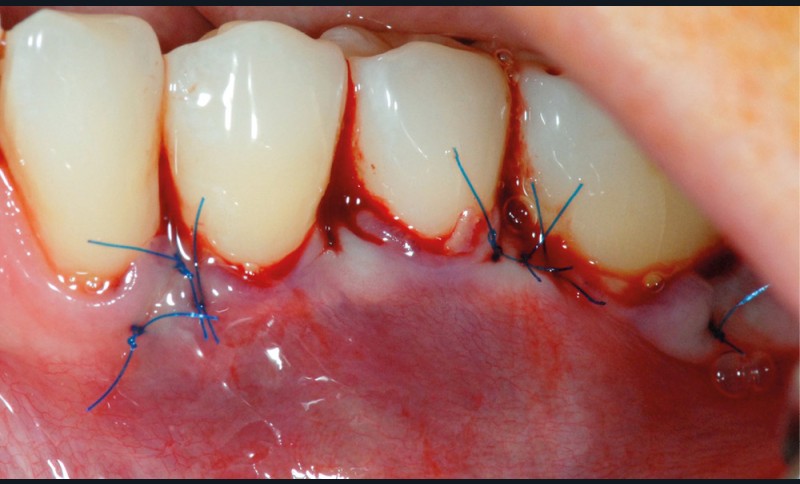

Cette technique permet de recouvrir des récessions gingivales contiguës par une traction coronaire après une dissection partielle superficielle au-delà de la ligne muco-gingivale. Grâce à un jeu d’incisions des papilles, les incisions de décharge ne sont pas nécessaires. Un greffon conjonctif prélevé au palais selon la technique de l’enveloppe [3] est placé sur les récessions et suturé en même temps que le lambeau par des points suspendus [4].

Dans notre cas clinique, l’intervention a duré un peu moins d’une heure.